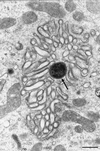

In vitro or animal models have been used to investigate the pathogenesis of Helicobacter pylori infection. However, extrapolation to humans of results obtained with these heterologous models remains difficult. We have developed a new model for the study of H. pylori infection that uses human entire embryonic stomachs engrafted in nude mice. At 80 days after implantation, 22 of these xenografts, which exhibited a mature gastric epithelium, were inoculated with 10(7) to 10(8) CFU of either H. pylori LB1, a freshly isolated H. pylori strain (n = 12), or H. pylori ATCC 49503 (n = 10). After 12-week examination, H. pylori LB1 persistently colonized the antrum of all inoculated grafts, as assessed by culture (mucus and mucosa), immunohistochemistry (mucosa), and a rapid urease test (mucus). H. pylori ATCC 49503, either before or after in vivo passage, permitted only a transient 2-week colonization in one of the five inoculated grafts in both groups. Colonization was always associated with an increase of gastric juice pH. A mild neutrophil infiltration of the gastric mucosa was noted solely in infected grafts. Transmission electron microscopy showed adherence of H. pylori organisms to epithelial cell surface. In six animals, intracytoplasmic location of this bacterium was observed in the antrum or the fundus. These results allow us to propose this model as a new ex vivo model for the study of specific H. pylori-gastric cell interactions.